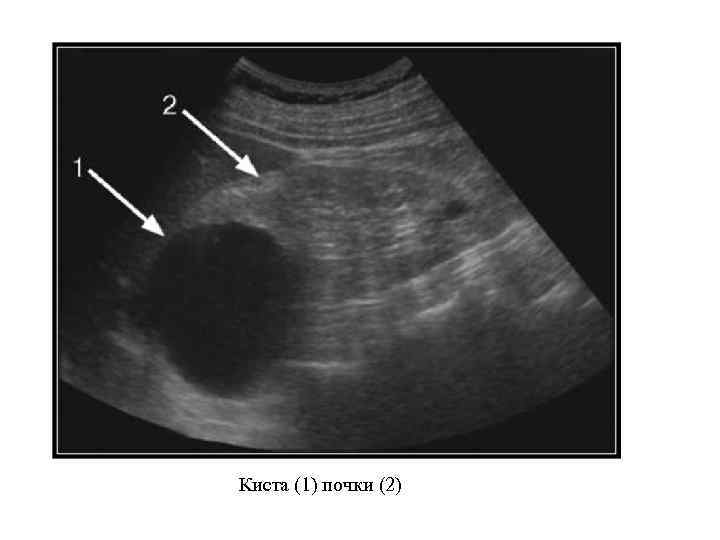

Аномалии структуры почек Дисплазия почки. Мультикистоз почки. Поликистоз почек: поликистоз взрослых; поликистоз детского возраста. Солитарные кисты почек: простая; дермоидная.

Аномалии структуры почек Дисплазия почки. Мультикистоз почки. Поликистоз почек: поликистоз взрослых; поликистоз детского возраста. Солитарные кисты почек: простая; дермоидная.

а — поликистоз; б — мультикистоз; в — солитарная киста; г — мультилокулярная киста; д —губчатая почка; е — чашечковый дивертикул в верхнем полюсе почки, сообщающийся с чашечнолоханочнойсистемой"

а — поликистоз; б — мультикистоз; в — солитарная киста; г — мультилокулярная киста; д —губчатая почка; е — чашечковый дивертикул в верхнем полюсе почки, сообщающийся с чашечнолоханочнойсистемой"

Поликистоз почек

Поликистоз почек

Киста (1) почки (2)

Киста (1) почки (2)